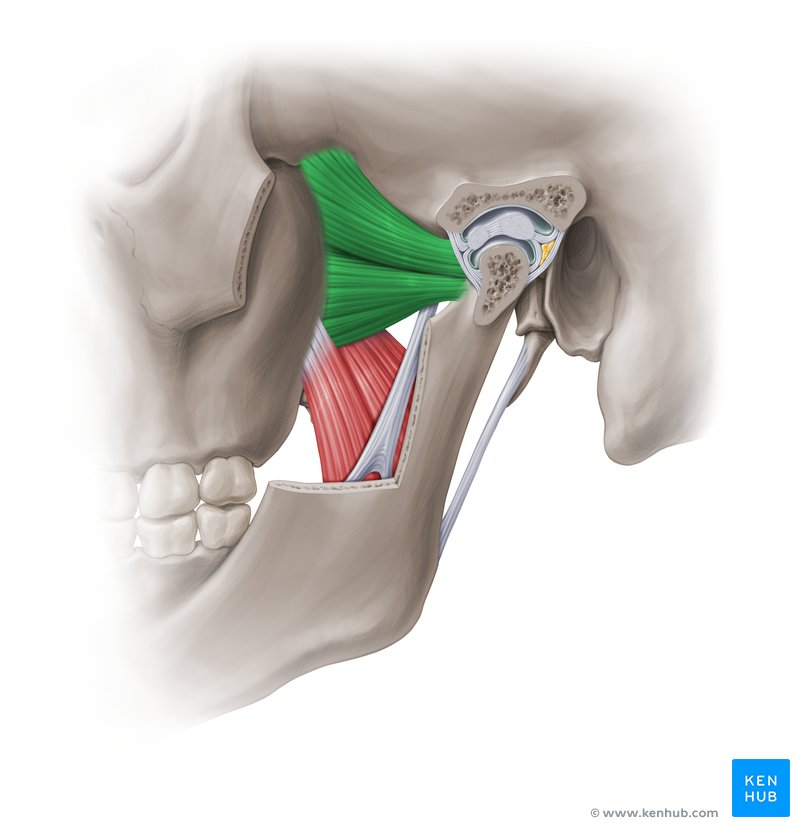

m temporalis

m masseter

m pterigoideus medialis

m pterigoideus lateralis